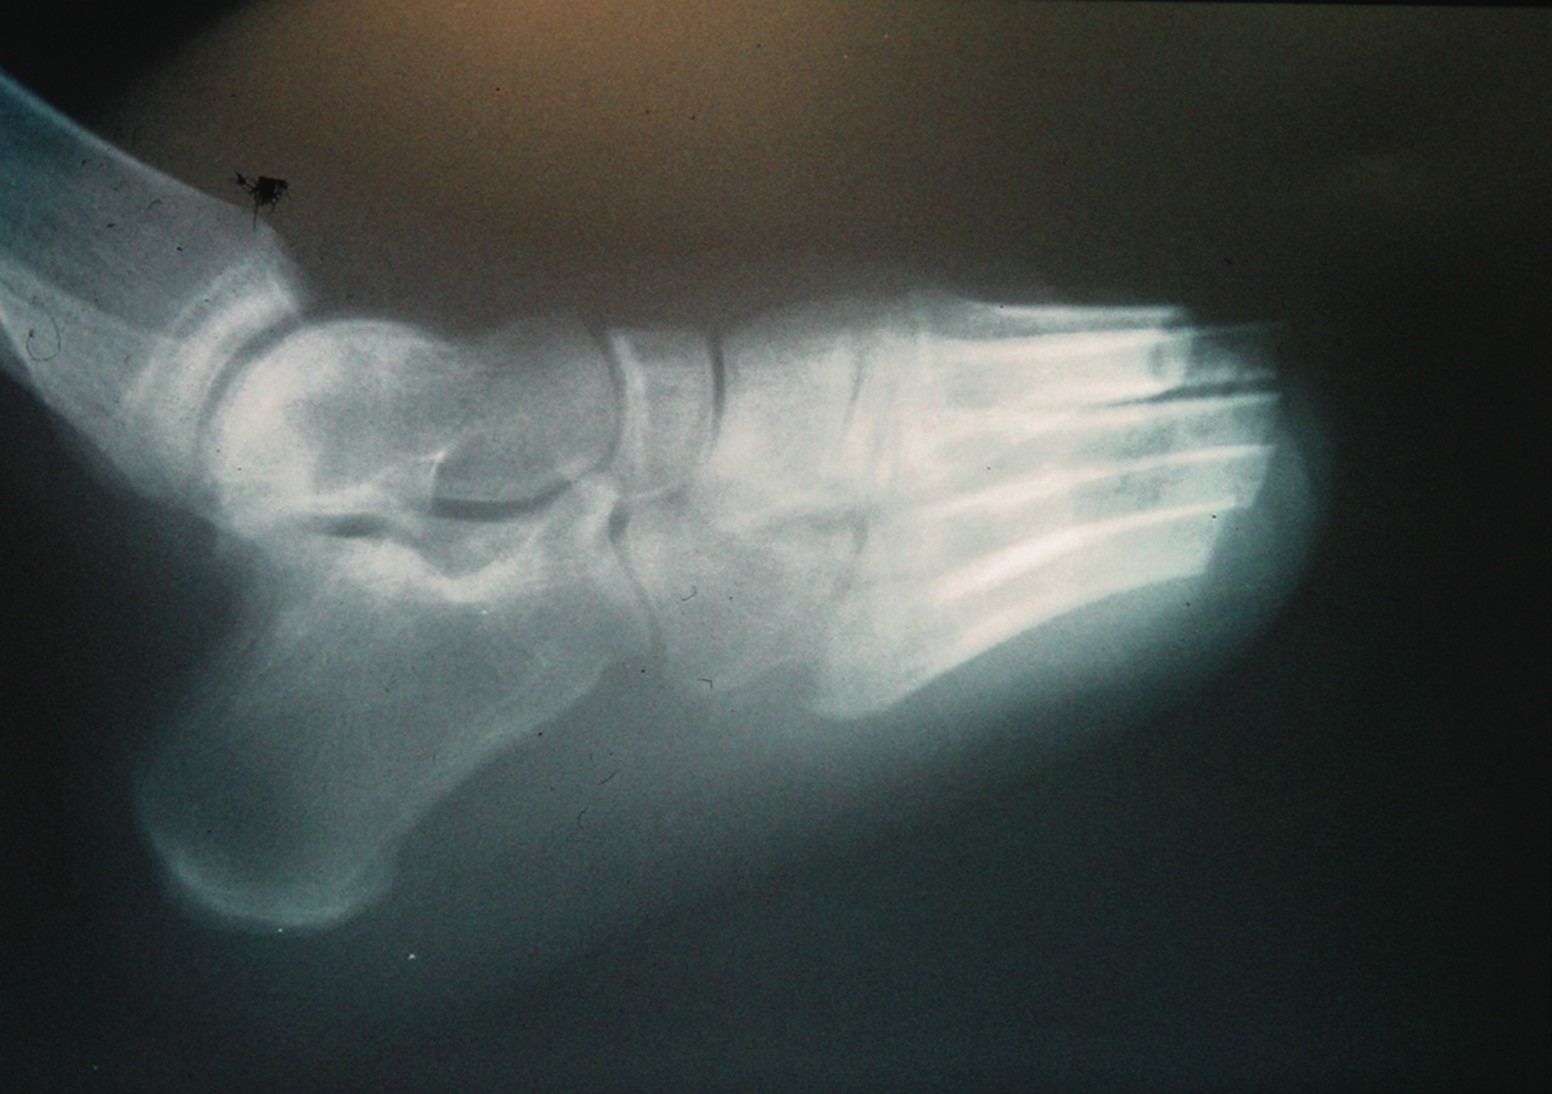

A 58-year-old patient presents with a 20-year history of type 2 diabetes. His control has been mediocre with hemoglobin A1c levels around 8.5 percent. He has been treated for hypertension and is being monitored by cardiologists. The patient has a history of chest pain but no events of myocardial infarction or cerebrovascular accidents (CVA). He developed a pressure ulceration of his fifth toe that led to osteomyelitis. Preoperative indices for healing were borderline. Surgeons amputated the toe but it failed to heal. Peripheral vascular surgeons performed an angioplasty and the patient’s foot perfusion improved. He did require an amputation of the adjacent fourth toe due to progressive necrosis of the wound edges from the previous amputation. This wound also dehisced but improved slowly over time, probably due to the vascular intervention. In the meantime, his chest pain became worse and he required a coronary angioplasty. The patient also required prolonged local foot wound care to achieve healing. After two foot procedures, a vascular intervention, cardiac complications, lengthy wound care and a disability that lasted over a year, the foot finally healed and the patient returned to work in his previous occupation. He wears accommodative shoes and sees his podiatrist for regular follow-up visits. This case illustrates a difficult protracted course of limb salvage but nevertheless, the patient successfully returned to productive community activity. In contrast, a 62-year-old patient had a similar diabetes history but more vascular problems and evidence of the early stages of renal failure. He had a history of myocardial infarction and coronary artery angioplasty before a minor injury to his second toe resulted in distal cyanosis and ischemic pain. The toe was cool, there was no break in the skin and there were no pulses in the foot. Surgeons performed peripheral vascular stenting and the patient’s ankle brachial artery indices improved. However, the aforementioned toe remained cool and painful. Despite a second toe amputation, the wound still failed to heal. The vascular service performed yet another angioplasty as well as extensive debridement of bone and soft tissue, yet little improvement in the wound occurred. Amputation to the Syme’s level was recommended but the patient was adamant about making more efforts to try to save more of the foot. He proceeded to undergo a transmetatarsal amputation. The amputation site presented a non-viable wound that clinicians treated for over a week before the patient demonstrated signs of progressive necrosis and sepsis. Finally, the patient underwent a transtibial amputation. Six weeks later, surgeons fitted the patient with a prosthesis and he began rehabilitation. Although he took early retirement, the patient has returned to independent community ambulation. Had the surgeons performed the transtibial amputation after the failed toe amputation, three operations would have been eliminated from this patient’s five-stage below-knee amputation. His case illustrates the fact that in spite of our best efforts, all limbs with diabetic complications are not salvageable. Both patients had low normal levels of serum albumin at approximately 3.0 gm/dl. Their total lymphocyte counts were both above 1,700. Their ankle brachial indices were about 0.3 before their vascular procedures and 0.45 afterward. They both had heart disease but who had more severe heart disease? The 58-year-old patient had worse control but the 62-year-old patient had early renal disease. If one measured the degree of control, nutritional status, renal function and cardiac function, would a significant difference between the two in any of these parameters be predictive of their eventual outcome? Right now, we do not know but the fact that many limb salvage attempts fail suggests we should find out.